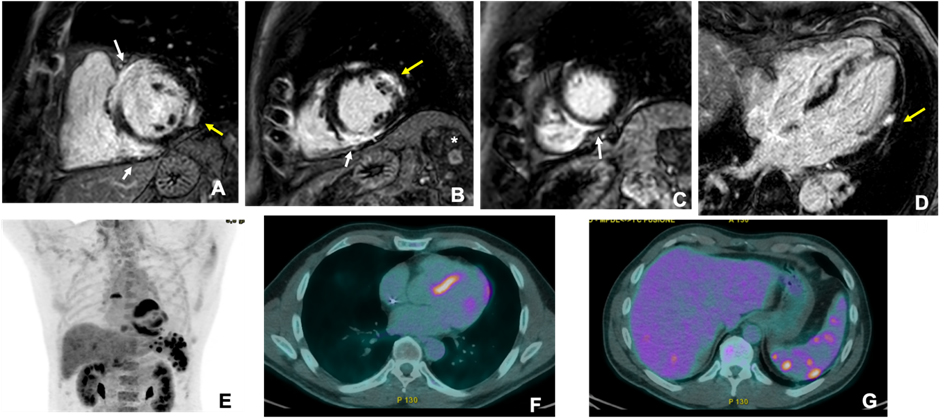

CMR and PET are the primary imaging modalities for CS and can be used to assess myocardial changes and disease activity. CMR provides comprehensive information on cardiac anatomy, function, and myocardial composition, including edema, fibrosis, and scarring [47]. However, CS can mimic various cardiomyopathies, with nonspecific findings such as localized dyskinesia, septo-basal thinning, or pericardial effusion [48]. T2-weighted imaging detects myocardial edema, typically in the septum [49]. Thus, late gadolinium enhancement (LGE) is crucial for diagnosing CS, revealing fibrosis in patchy, multifocal patterns sparing the endocardium [50]. As shown in Fig. 2, LGE is often found in the basal and mid-septum, with potential extension to the right ventricle [51], and it is a key prognostic factor [17]. Studies have shown a significant association between LGE and adverse outcomes, including ventricular arrhythmias and mortality [52, 53].

Fig. 2. Cardiac magnetic resonance (CMR) and 18F-fludeoxyglucose (FDG)-positron emission tomography (PET) images of a male adult (51 years old) 24 hours after resuscitation from sudden cardiac death. CMR (upper panels) showed hypertrophy of the mid-basal interventricular septum, associated with patchy areas of late gadolinium enhancement (LGE) with a subepicardial pattern involving the entire septum, especially at the junction point with the right ventricle, «hook sign», (white arrows in (A–C)). Smaller areas of subepicardial (LGE) were also evident on the lateral wall (yellow arrows in (A,B,D)). Additionally, magnetic resonance imaging (MRI) showed multiple enhancing nodules in the spleen (asterisk in (B)), suggestive of granulomas. The patient also underwent 18F-FDG-PET (lower panels), which showed marked uptake in the site of LGE (E,F) and focal areas of uptake on the liver and the spleen (G).

Nuclear imaging, particularly cardiac 18F-fludeoxyglucose (FDG)-PET, plays a central role in detecting myocardial inflammation, with high sensitivity (94–100%) [54]. 18F-FDG-PET is more sensitive than Gallium scintigraphy, Thallium, or Technetium-99m single-photon emission computed tomography for detecting myocardial inflammation [55]. To suppress normal myocardial glucose uptake, patients undergo a specific high-fat, low-carbohydrate diet followed by fasting, which can sometimes lead to inconclusive results in 10–15% of cases [56, 57]. PET scans often show patchy or diffuse myocardial uptake, particularly in the basal septum (Fig. 2). A combined perfusion scan enhances specificity, revealing perfusion defects associated with fibrosis or microcirculation abnormalities [58]. Both “mismatch patterns” of FDG uptake and right ventricular involvement can predict adverse cardiovascular outcomes [59, 60]. PET is also used to monitor treatment responses to immunosuppression [61]. Hybrid PET/MRI scanners combine LGE and FDG uptake and offer a deeper characterization of CS and differentiation between active and inactive disease [62]. Thus, using hybrid PET/MRI scanners also allows for better prognostication, with a lower radiation dose and higher diagnostic performance than individual PET/computed tomography (CT) [63, 64].